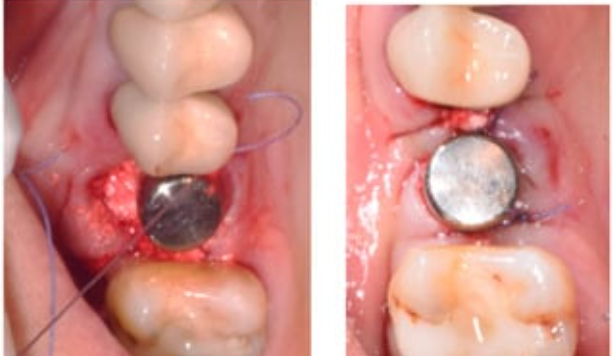

糖尿病是牙种植的相对禁忌症,并非所有糖尿病患者都无法进行种植治疗。通过严格的患者选择和术前术后管理,糖尿病患者仍可获得满意的种植成功率。因此,糖尿病患者是可以进行种植牙手术的。

通常情况下,在无严重糖尿病并发症条件下,只要血糖水平控制得好,种植手术是可以做的。血糖控制水平的两个重要指标分别是空腹血糖和糖化血红蛋白。其中。糖化血红蛋白评估过去2-3个月平均血糖水平,是判断血糖控制状态最有价值的指标。有文献表明,当糖尿病患者空腹血糖值小于8.0和糖化血红蛋白值小于8%,是口腔种植的适宜时机。

如果血糖控制不佳,医生可能会建议暂时推迟手术,并通过饮食、药物或胰岛素等方式先把血糖控制在合理范围内。因此,对糖尿病患者来说,种植牙并不是禁忌,关键在于血糖的良好管理。